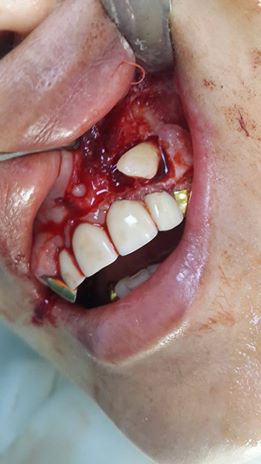

The patient turned to the doctor with the presence of a retinas tooth. The tooth was surgically removed.